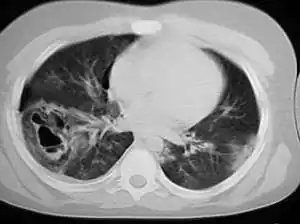

Computed tomography

Computed tomography (CT scanning) is a more sensitive test for pulmonary contusion,[6][33] and it can identify abdominal, chest, or other injuries that accompany the contusion.[38] In one study, chest X-ray detected pulmonary contusions in 16.3% of people with serious blunt trauma, while CT detected them in 31.2% of the same people.[45] Unlike X-ray, CT scanning can detect the contusion almost immediately after the injury.[43] However, in both X-ray and CT a contusion may become more visible over the first 24–48 hours after trauma as bleeding and edema into lung tissues progress.[46] CT scanning also helps determine the size of a contusion, which is useful in determining whether a patient needs mechanical ventilation; a larger volume of contused lung on CT scan is associated with an increased likelihood that ventilation will be needed.[43] CT scans also help differentiate between contusion and pulmonary hematoma, which may be difficult to tell apart otherwise.[47] However, pulmonary contusions that are visible on CT but not chest X-ray are usually not severe enough to affect outcome or treatment.[37]